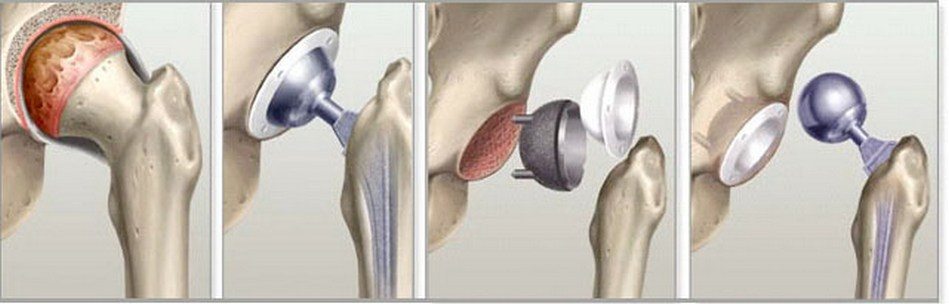

Эндопротезирование

Коллапс субхондральной кости, характерный для 4 стадии асептического некроза, является показанием для однополюсного эндопротезирования — замены головки бедренной кости искусственным имплантатом. Тотальное хирургическое вмешательство показано при уже развившемся тяжелом коксартрозе. Эндопротезами заменяются и головка бедра, и вертлужная впадина.

Операция проводится под общим наркозом. Проксимальная часть кости спиливается под углом 45 градусов, а после формирования канала устанавливается эндопротез, фиксируется цементом или бесцементным способом. Рана ушивается, дренируется. Длительность госпитализации — до 2 недель.